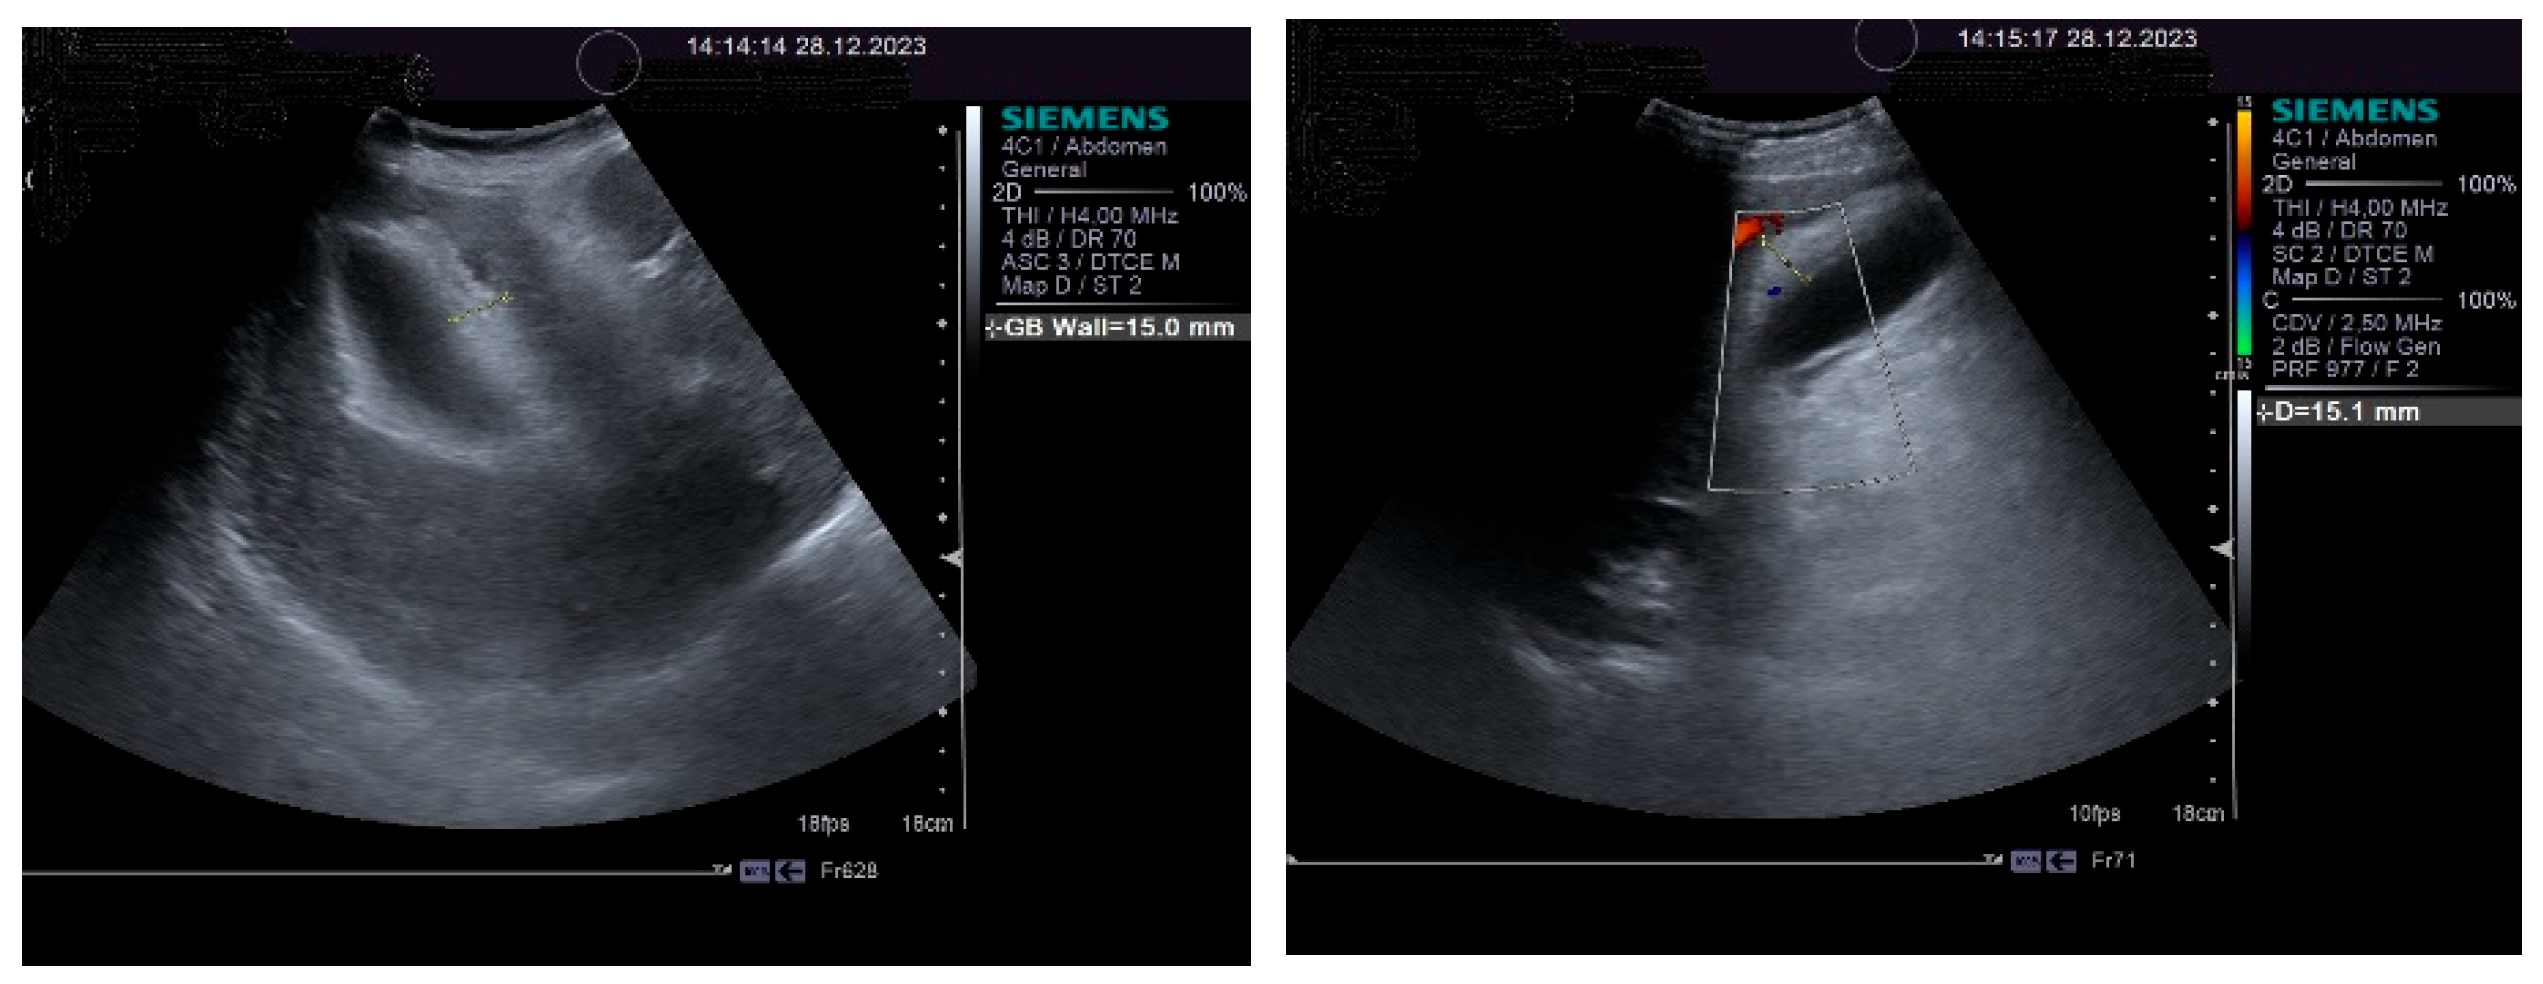

On physical examination, a mild tenderness of the right upper abdominal quadrant, a firm hepatomegaly, a palpable inferior pole of the spleen and a slight increase in abdomen volume were found. No other liver stigmata were noticed. The abdominal duplex ultrasound examination, performed with Siemens high-resolution equipment, showed hepatomegaly with a discrete irregularity of the liver surface, heterogeneity of the liver texture, the caudate lobe at the upper limit, filiform hepatic veins, massive thickening of the gallbladder wall, ascites in small quantity and mild splenomegaly with turbulence of the venous flow in the hilum. The question about liver cirrhosis was asked. Various aspects of the 2D ultrasound examination of the liver are depicted in Figure 2.

The pulsed Doppler ultrasound revealed a patency of the main portal vein as well as of the left and right portal branches and decreased, demodulated hepatopetal portal venous flow, with mildly decreased respiratory variability in the amplitude of the portal vein flow. The Dopler aspects of the liver and spleen are illustrated in Figure 4.

An important role in the imaging diagnostic approach of SOS/VOD is played by ultrasonography. According to some studies, it seems that ascites and gallbladder wall edema represent independent predictors in SOS/VOD diagnosis. Some authors reported that the thickness of the gallbladder wall correlated well with the HVPG. This particular aspect of the markedly thickened GB wall was also observed in the presented patient, associated with ascites and increase in the HVPG. Pulsed Doppler ultrasound is also useful for suggesting SOS/VOD, based on the study of the venous portal flow, which can be decreased or reversed. A significant increase in the HARI may also be associated with liver injury. Hepatic and portal flow anomalies revealed by duplex examination seem to correlate with the HVPG. However, as we have also noted, the reversed portal venous flow is not always recorded and, therefore, one cannot exclude SOS/VOD based on the absence of the hepatofugal portal flow sign [28]. The patient that we have presented in this case report displayed no reversed portal venous flow, but increased values of the HARI.

Figure 4. Doppler examination. Liver: pulsed Doppler of the portal vein (left). Spleen: color Doppler of splenic vein (right).